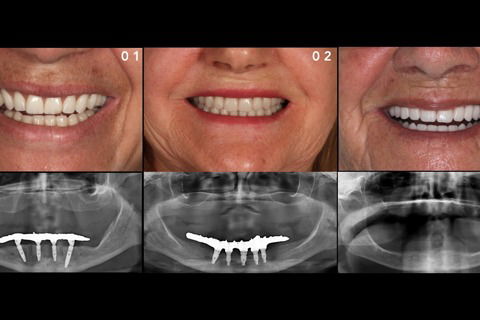

Sorriso final

Foto 17 Sorriso final